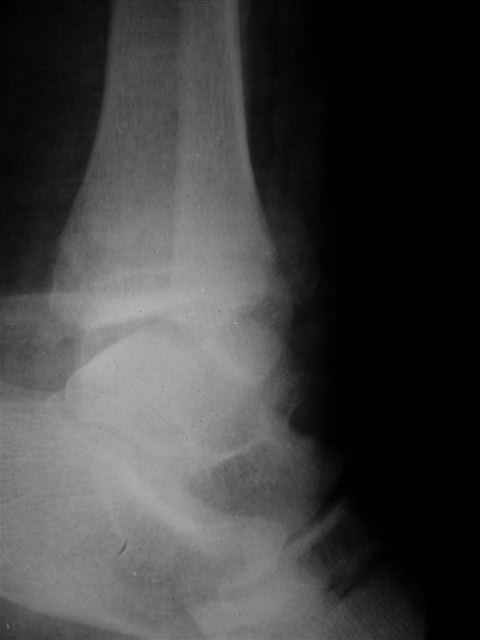

> Если Вас не затруднит, пришлите, пожалуйста, рентгенограммы. Я

> интересуюсь тактикой лечения повреждений голеностопного сустава.

> Хочется посмотреть, как лечат коллеги.

Я предупреждал, что ничего сверхъестественного. Каюсь, что одна из спиц прошла несколько дальше, чем нужно было, но главное - перелом стабилизирован и больной работает суставом в полном объёме, несмотря на представленную раннее травму коленного сустава.